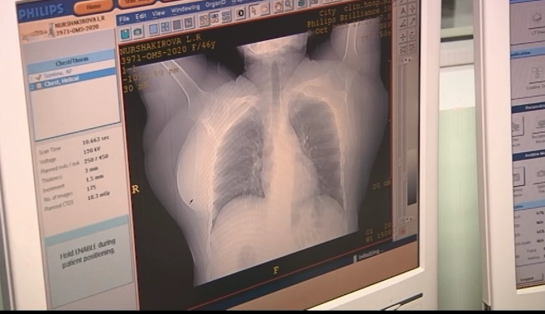

Фото: КТВ-ЛУЧ